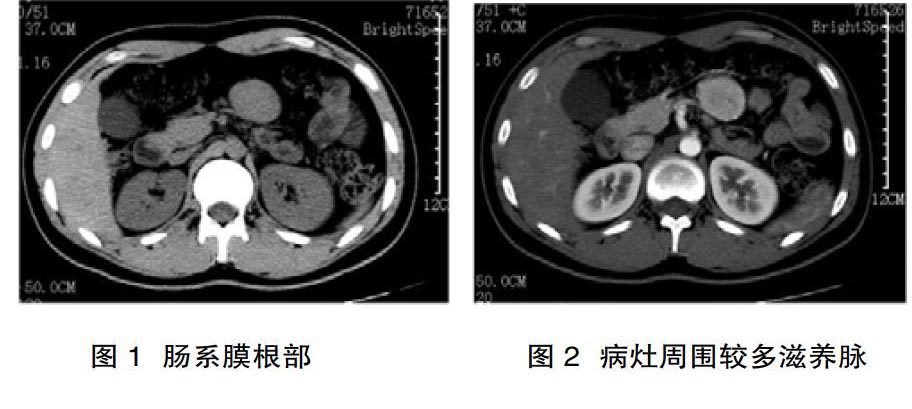

7例中4例位于肠系膜根部(图1),3例位于腹膜后(图5)。肿块均呈圆形、椭圆形或梭形,大小不一,直径4.0~7.6 cm,平均5.9 cm,边缘规则或有浅分叶,边缘光滑,与周围结构分界清楚。

对所有病灶进行CT平扫均为软组织密度,CT值为33~58 HU,平均42 HU,病灶密度均匀,增强扫描各病灶均有明显强化,以动脉期为著,CT值为90~150 HU,平均112 HU,增强程度与邻近大血管相似,4个病灶周边显示较多滋养动脉(图2、图7)。2例病灶动脉期内部可见裂隙状低密度区,门静脉期及延迟扫描中心低密度区范围缩小(图2、图3、图4 )。

图1、图2、图3、图4 肠系膜根部局限透明血管型Castleman病。图1为CT平扫, 病灶成类圆形,密度尚均匀,边界清晰;图2增强扫描动脉期明显强化,中心见裂隙状低密度影,病灶边缘见多发滋养血管影;图 3、图4门静脉期及延迟期持续强化,中心星状低密度区逐渐填充,强化程度与腹主动脉相似,密度均匀。